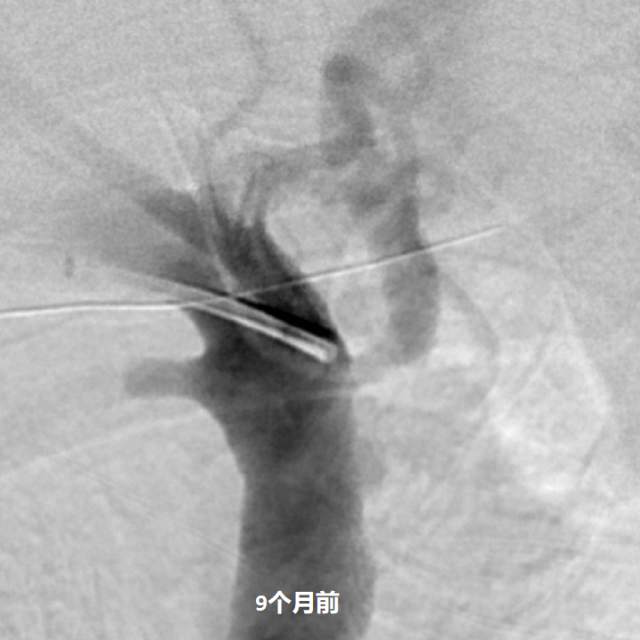

最近,儿子带老人家过来复查,检查发现右侧椎动脉起始部的狭窄越来越重,和9个月前相比,简直判若两人(管),左侧椎动脉又先天发育不好……,看来保守治疗吃药不太行,还得需要外科干预